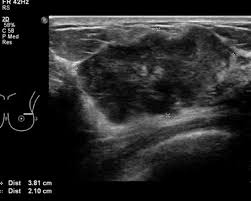

• US / MRI can help in some settings